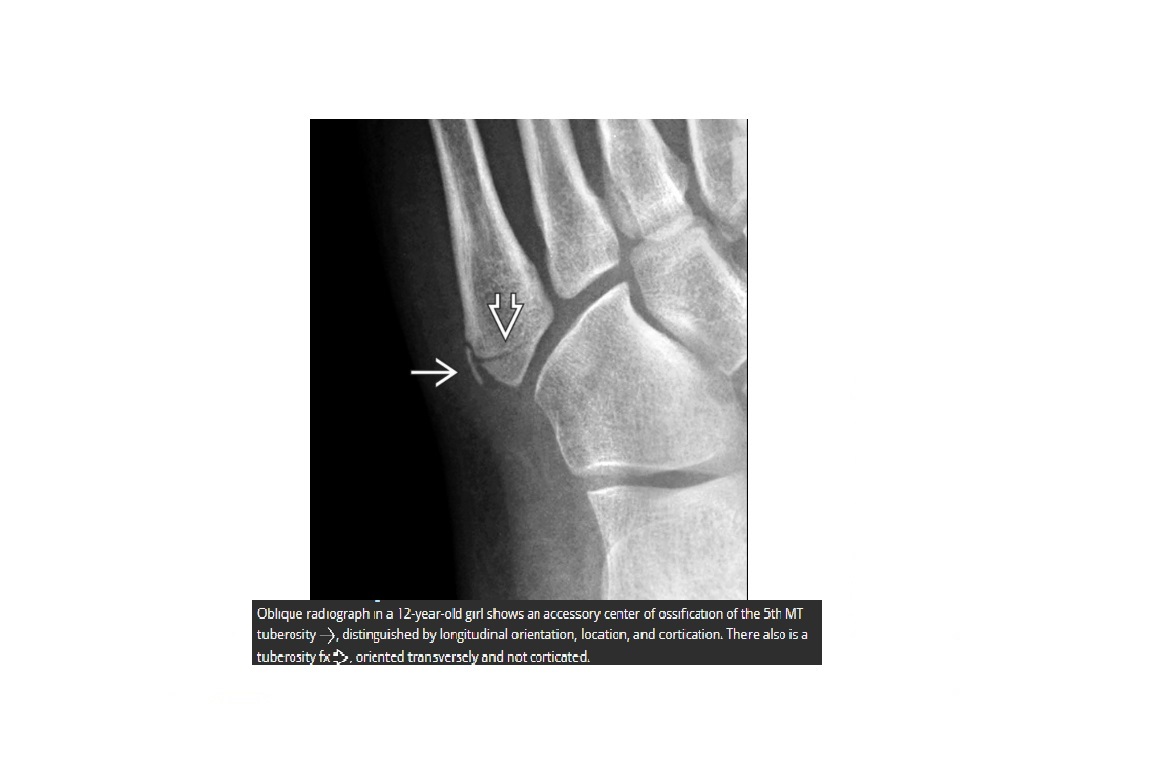

Jones Fracture?

Fracture base of 5th metatarsal

**1.5cm distal to the tuberosity @ metaphysis-diaphysis junction

What is the most common fracture of the base of 5th metatarsal?

Avulsion

Peroneus brevis